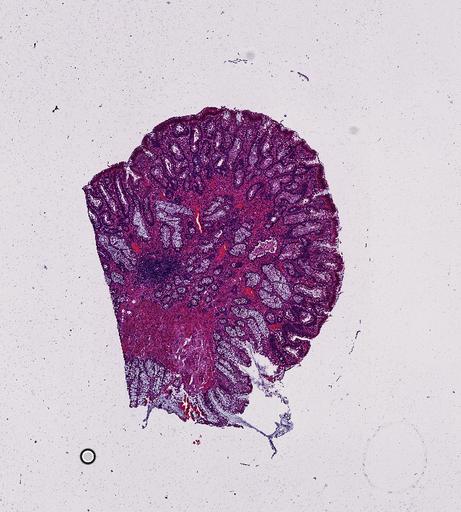

High‑resolution three‑dimensional (3D) tissue atlases promise to redefine how we study cellular architecture‑function relationships in human tissues. Large-scale consortia such as the Human Bimolecular Atlas Program (HuBMAP) systematically build detailed 3D organ maps by profiling serial tissue sections with single-cell spatial technologies. However, an accurate and efficient reconstruction method that can handle atlas-scale datasets remains elusive. We introduce Space-map, an open-source method that integrates single‑cell coordinates with optional histological image features to assemble serial sections into 3D models. Space‑map combines multi‑scale feature matching with large‑deformation diffeomorphic metric mapping, delivering global reconstructions while preserving local micro‑anatomy. To demonstrate the capability of Space-map, we generated a serially sectioned spatial transcriptomics (Xenium, ~2.9M cells) dataset and a spatial proteomics dataset (CODEX, ~2.4M cells). Applying Space-map to these single-cell spatial maps, we built three 3D models for both diseased (colon polyp) and reference colon tissues. These high-resolution 3D models showcase the intricate structure of the human colon across different states. Space-map is fast and highly efficient. We demonstrated its performance and accuracy using in‑house and public datasets. The result shows that Space‑map is 10 times faster and ~2‑fold more accurate than PASTE and STalign, making 3D atlas reconstruction more accessible. Our study provides a new robust and user-friendly software available at https://github.com/a12910/spacemap that can be easily applied for constructing molecular 3D tissue maps of human organs at single-cell resolution.